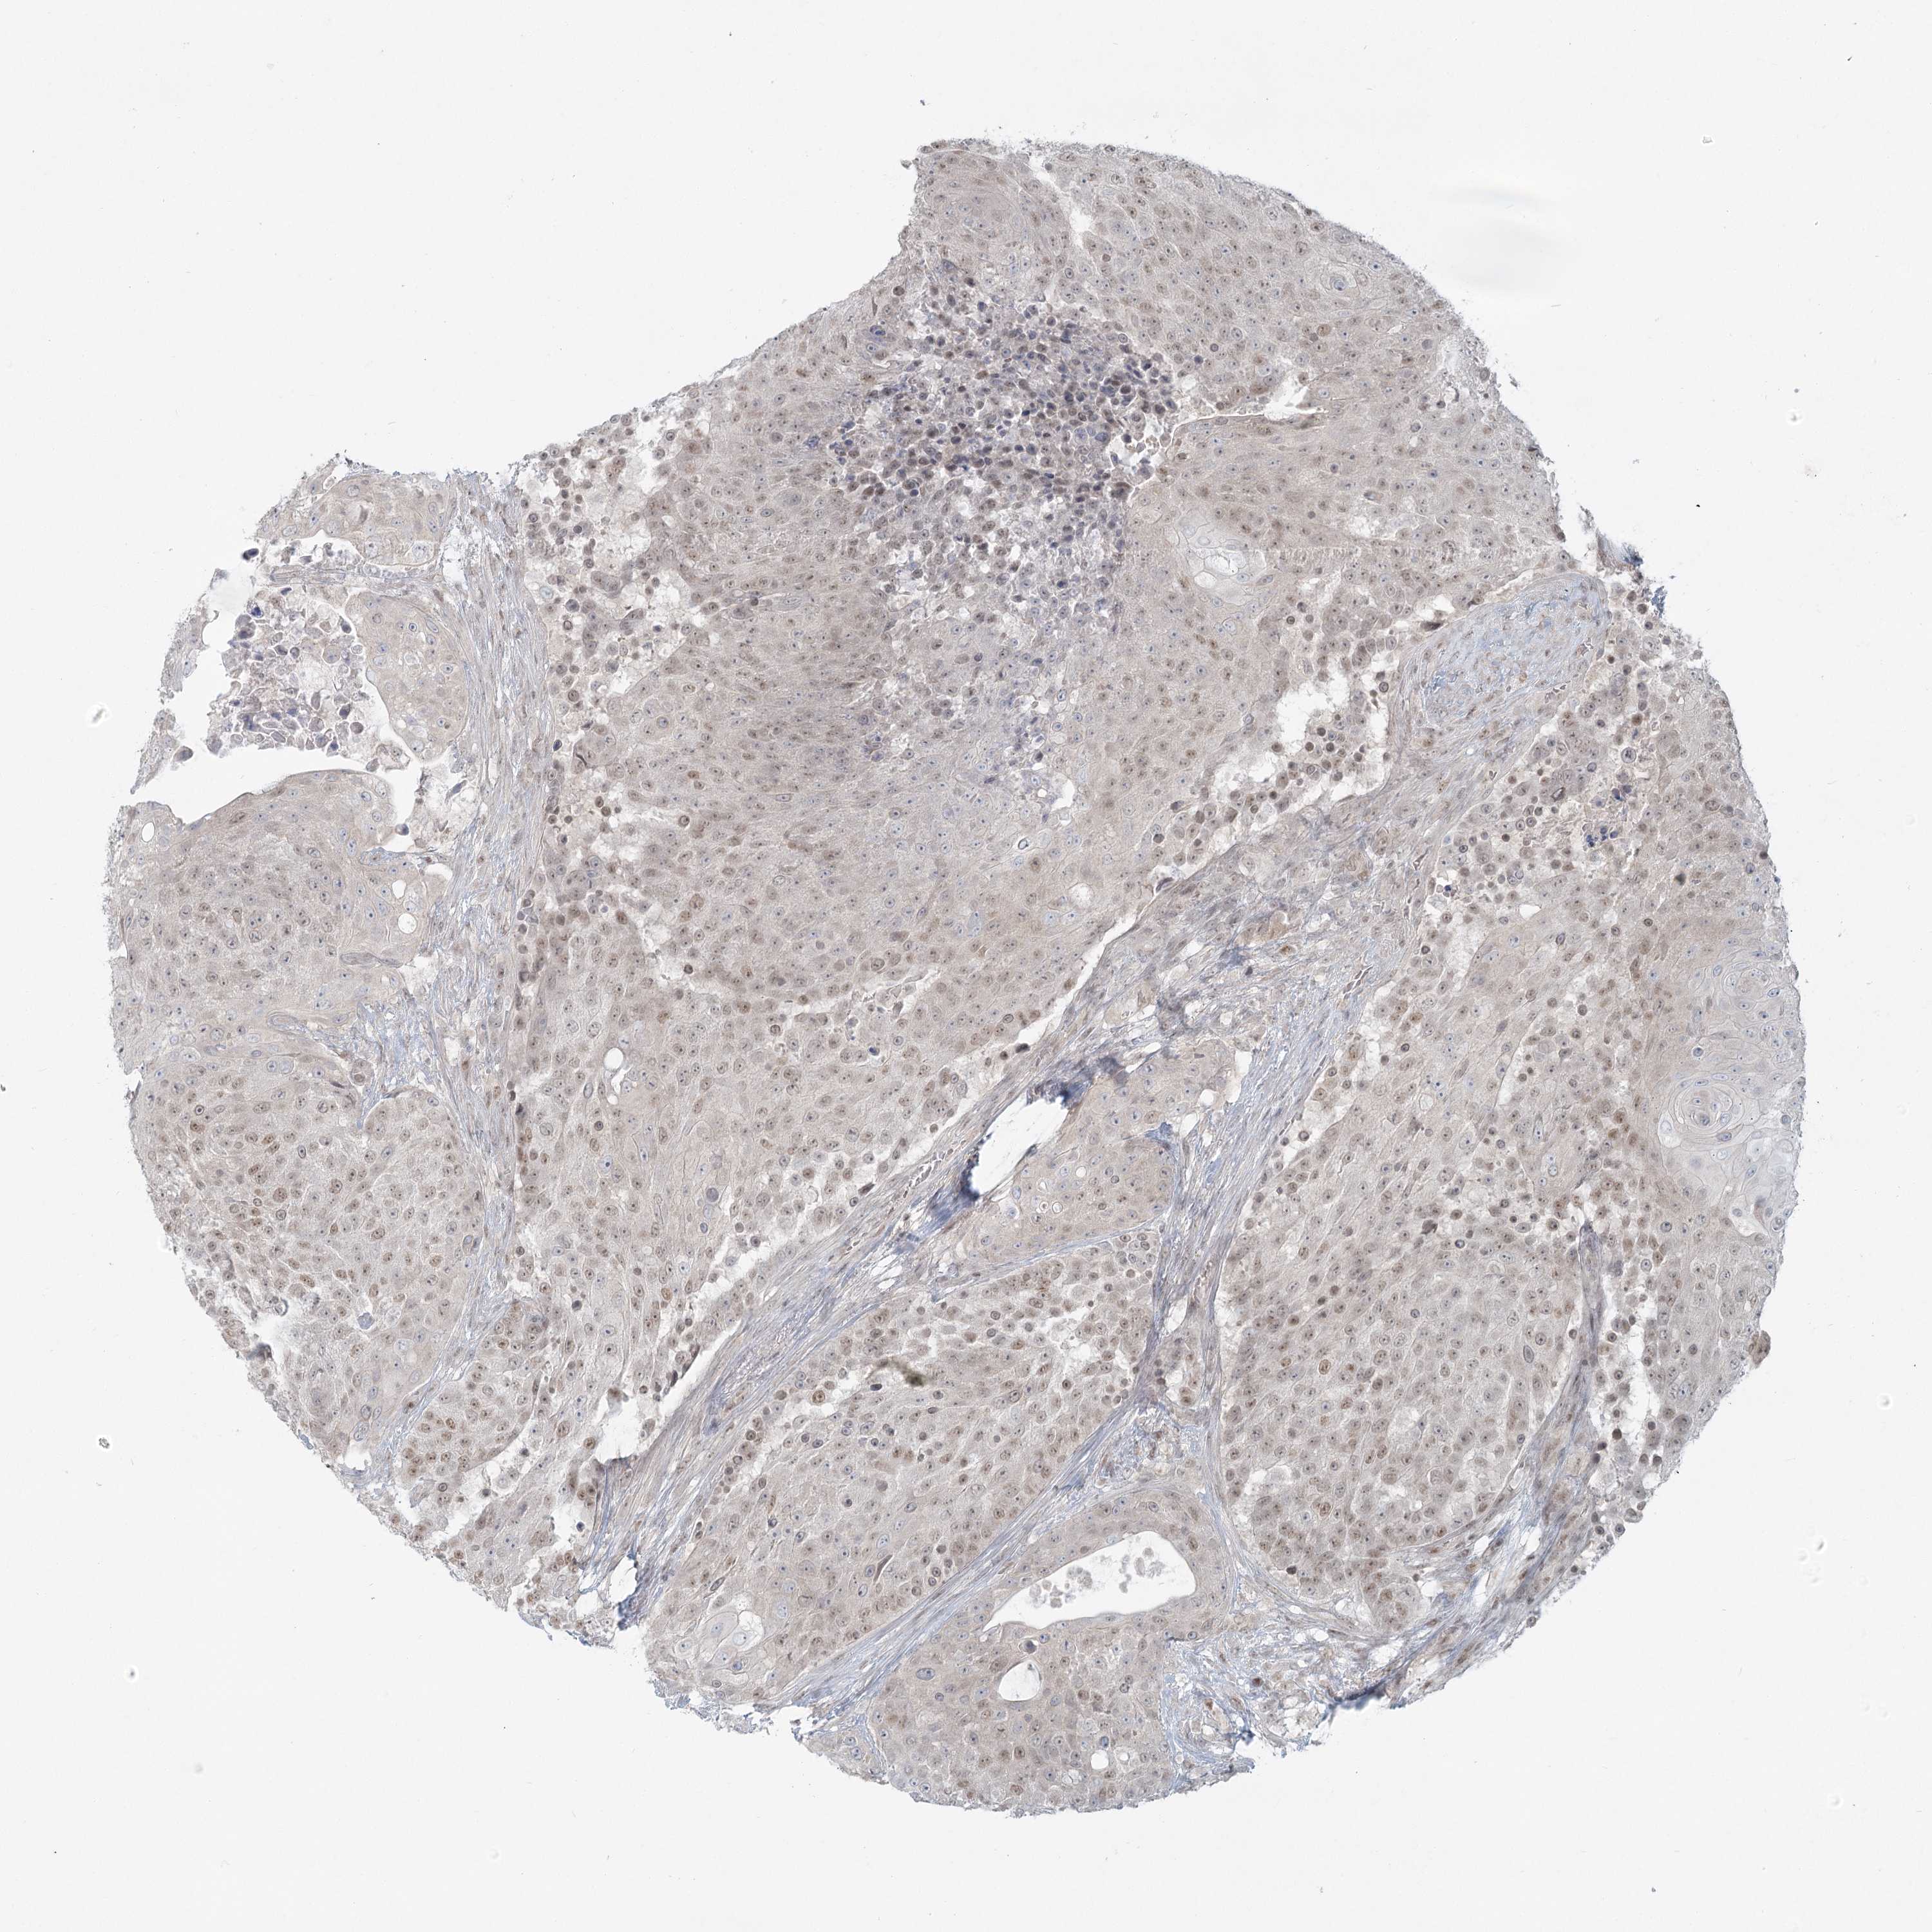

UROTHELIAL CANCER - Protein expressioni

A mouse-over function shows sample information and annotation data. Click on an image to view it in a full screen mode. Samples can be filtered based on level of antibody staining by selecting one or several of the following categories: high, medium, low and not detected. The assay and annotation is described here.

Note that samples used for immunohistochemistry by the Human Protein Atlas do not correspond to samples in the TCGA dataset.

Antibody stainingi

Antibody staining in the annotated cell types in the current human tissue is reported as not detected, low, medium, or high, based on conventional immunohistochemistry profiling in selected tissues. This score is based on the combination of the staining intensity and fraction of stained cells.

Each image is clickable and will lead to virtual microscopy that enables deeper exploration of all samples and also displays staining intensity scores, fraction scores and subcellular localization as well as patient and tissue information for each sample.

Antibody HPA037367

Staining

High

Medium

Low

Not detected

Intensity

Strong

Moderate

Weak

Negative

Quantity

>75%

75%-25%

<25%

None

Location

Nuclear

Cytoplasmic/membranous

Cytoplasmic/membranous,nuclear

Urothelial carcinoma, Low grade

Urothelial carcinoma, High grade